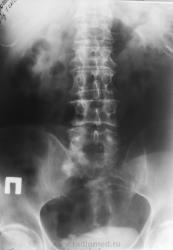

А Вы сделайте последний снимок через 12-24 часа от момента начала исследования...да с небольшим поворотом (левый бок чуть приподнять), вот тогда и посмотрим, то ли это тот "ежик" на уровне нижнего края S1 или та тень, что в малом тазу....то что камень в мочеточнике сомнений нет...но на что идти урологу...вот в чем вопрос.

Мне кажется, неоднородный камень или группа камней находится в устье правого мочеточника. Осталось неясным почему "оно" померкло на последнем снимке. Но Людмила Григорьевна умеет создать проблему на ровном месте, сама того не желая)). А в крестце вижу только очаг остеосклероза.

Виктор Григорьевич, проблема в том, что не факт, что через 12-24 часа поймаем контрастирование дистальной трети мочеточника. А КТ в нашем же отделении. Так что не стала выдумывать велосипед. Пациент получил диск, поедет в Тверь дробить руду

Петрович, Вы правы, но уже обжегшись, дую на кости - а вдруг там каменюка, а я за костные дела принимаю...